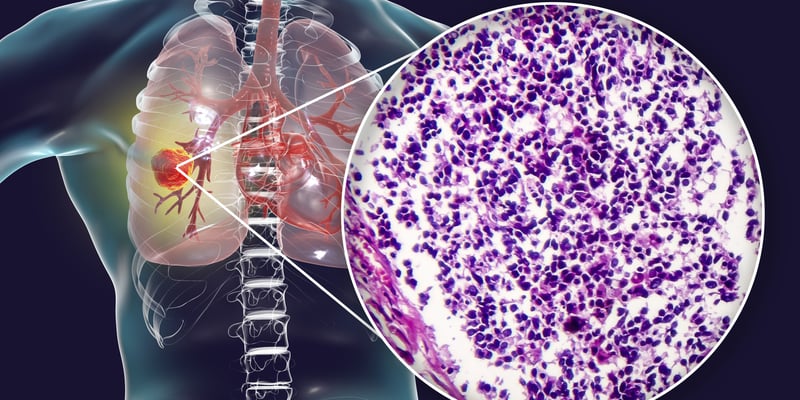

EGFR突变非小细胞肺癌在奥希替尼等EGFR-TKI后进展,下一步治疗常陷入选择困难。PD-L1×VEGF-A双抗联合化疗、HER3 ADC联合抗血管生成方案正在给耐药患者带来新的PFS、缓解率和安全性线索。 Read More... "EGFR突变肺癌TKI耐药后怎么办:双抗与HER3 ADC新方案"

KRAS G12C非小细胞肺癌耐药后还能用阿达格拉西布吗?ADEPPT研究提示,ECOG 0-1的老年患者可获得更明确缓解,而ECOG 2患者疗效有限但生活质量可能改善,副作用管理和用药可及性是决策关键。 Read More... "阿达格拉西布治疗KRAS G12C肺癌:ECOG评分决定获益"

KRAS G12C突变非小细胞肺癌一线治疗迎来重要研究信号:卡尔德拉西布联合帕博利珠单抗在PD-L1阳性患者中显示较高缓解率和较长PFS。疗效、适用人群、安全性、获批进展与患者该如何行动,一次讲清。 Read More... "KRAS G12C肺癌新药卡尔德拉西布联合免疫一线数据解读"

HER2突变非小细胞肺癌患者常面临脑转移、可用靶向药少和一线治疗选择不清的问题。宗艾替尼在Beamion LUNG-1研究中显示全身与颅内缓解,尤其为HER2 TKD突变晚期肺癌带来新的治疗线索。 Read More... "HER2突变肺癌一线靶向治疗:宗艾替尼脑转移疗效数据解读"

EGFR突变非小细胞肺癌用奥希替尼后,是否还要加局部巩固放疗?NorthStar研究提示,联合LCT可延长PFS,尤其胸部淋巴结和胸腔积液清除、放疗BED≥75 Gy的人群更可能获益。 Read More... "EGFR肺癌奥希替尼联合放疗:哪些患者PFS获益最大"

早期非小细胞肺癌不再是“确诊后尽快切除”这么简单。基因检测、PD-L1、EGFR、ALK、术前免疫联合化疗正在改变手术时机、切除范围和治疗顺序,患者最该弄清楚的是:先活检还是先手术、等待检测会不会耽误病情、哪些人需要多学科会诊。 Read More... "早期非小细胞肺癌手术怎么定?基因检测与术前治疗全指南"

早期非小细胞肺癌不能手术或不适合手术时,SBRT是重要根治手段。ASTEROID II期研究显示,SBRT后加入度伐利尤单抗可能减少肿瘤进展,但总生存获益尚未证实,副作用与适用人群更需谨慎评估。 Read More... "早期非小细胞肺癌SBRT联合免疫治疗:度伐利尤单抗能否降低进展风险"

ALK阳性非小细胞肺癌多线靶向治疗后耐药,下一步怎么选?TRI-611获FDA快速通道,提示ALK融合蛋白降解剂正在进入临床验证阶段。了解机制、入组条件、与洛拉替尼耐药后的潜在位置,能帮助患者更早规划治疗方案。 Read More... "ALK阳性肺癌耐药后新选择:TRI-611快速通道与临床试验解读"

广泛期小细胞肺癌一线治疗选择有限,复发快、进展快是患者最担心的问题。伦康依隆妥单抗联合斯鲁利单抗在Ⅱ期研究中显示较高缓解率和可控毒性,但仍需看清适用人群、获批状态、副作用管理与后续可及路径。 Read More... "小细胞肺癌一线新方案:伦康依隆妥单抗联合免疫治疗数据解析"